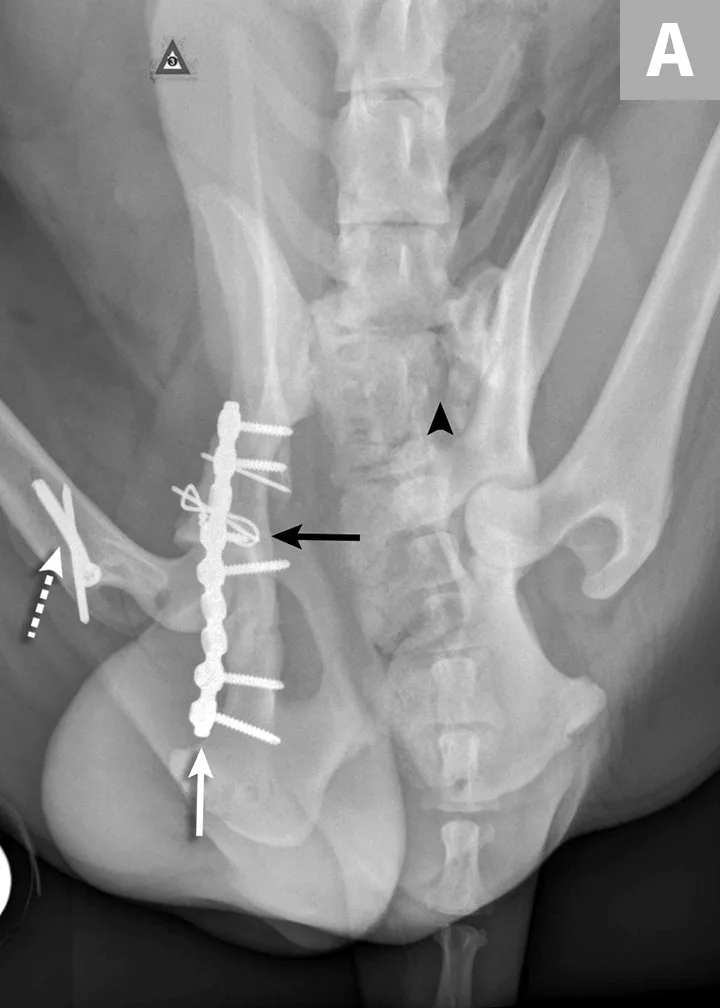

FIGURE 4A

Postoperative ventrodorsal (A) and lateral (B) projection images of the same dog in Figure 2. Fracture reduction was achieved with cross pins and a figure-eight hemicerclage wire (black arrows). Reduction was protected via application of a locking string-of-pearls neutralization plate (solid white arrows). To gain access to the full extent of the fracture, a greater trochanteric osteotomy was performed and stabilized with a positional screw and pin (dashed arrows). The ventrodorsal postoperative radiograph revealed a sacral fracture not previously appreciated (arrowhead). The fracture was successfully treated with conservative management.

Sacroiliac luxation and sacral fracture are the most common causes of multiple neurologic deficits in pelvic injuries3 and are caused by the location of the lumbosacral plexus ventral to the sacrum. Surgery for sacroiliac luxation depends on several factors, including degree of displacement, bilateral injury, and level of discomfort.21-23 Lag screw placement traversing >60% of the width of the sacrum is the most common surgical technique used for sacroiliac luxation.24,25

Ilial fracture stabilization can be accomplished using several methods individually or in combination; lateral or ventral plate stabilization with locking or nonlocking plates are the most common methods. Sciatic nerve injury can be associated with ilial fracture because of the location of the nerve medial to the ilial body. Care should be taken during fracture reduction and stabilization to avoid iatrogenic trauma to the nerve.26